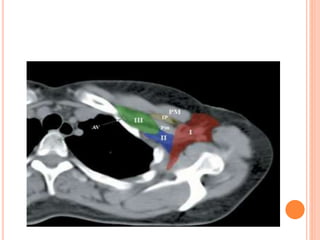

REGIONAL NODAL CONTOURING

SCF begins

Axillary level III begins

Axillary level II begins

Axillary level I begins

Axillary level I ends

IMC begins

IMC ends